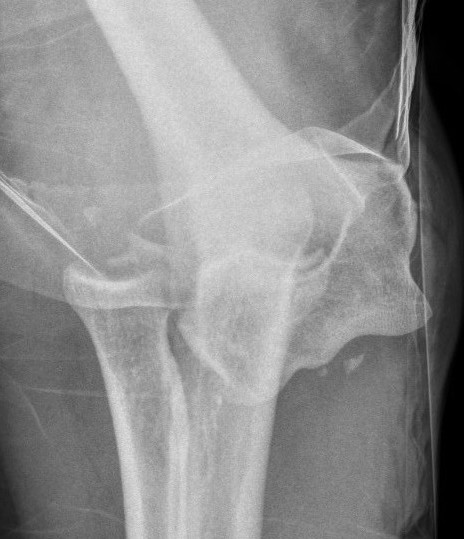

Elbow dislocation with radial head fracture

Management

Critical to elbow stability

Based upon Mason classfication